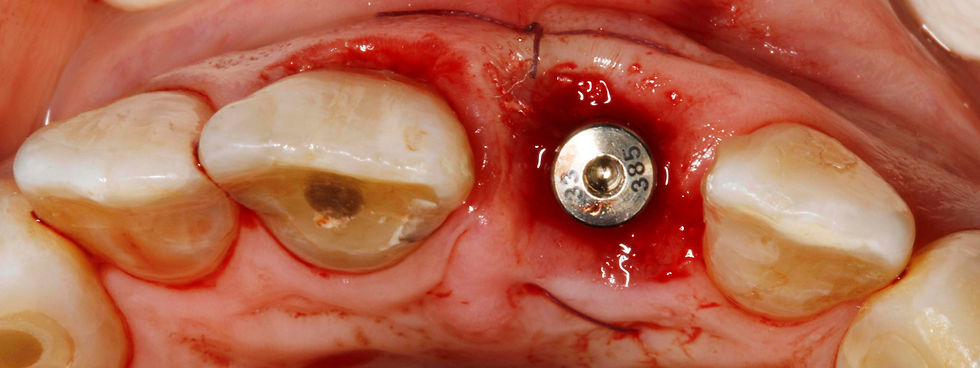

Prama implant in situ.

Positioning of a healing abutment and sutures.